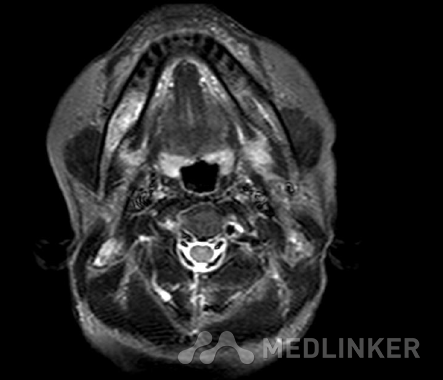

主诉:「发现枕颈部皮下肿物10年〕 病史:患者诉10年前发现右侧枕颈部皮下肿物,近1年增大明显,并伴有触摸痛,无红肿,无破溃。行MRI示右侧颈枕部皮下软组织包块并明显强化,性质待定。为求治疗来我院就诊,门诊以“枕颈部皮下肿 物”收入院。患者自入院,神志清,精神可,体重无明显改变,二便正常.

MR:(右枕颈部皮下)梭形细胞肿瘤,倾向为神经纤维瘤,建议做免疫组化辅助诊断。